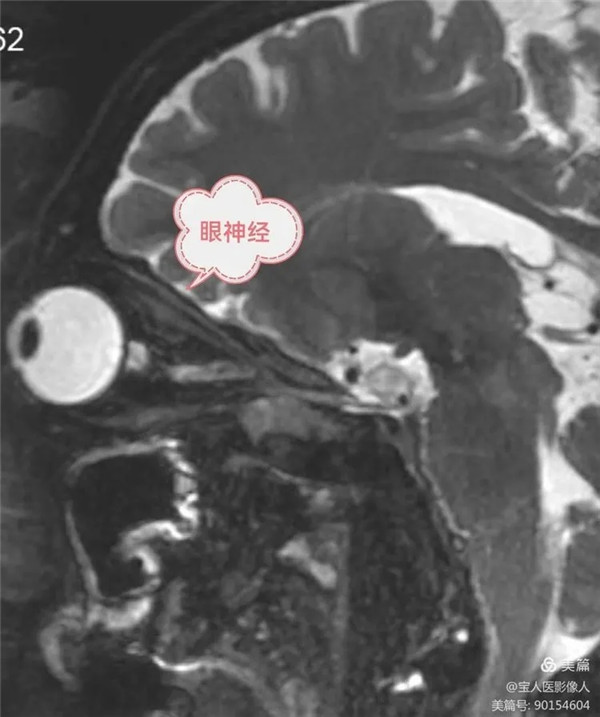

磁共振成像顯示三叉神經顱外段第一分支,眼神經

眼神經在三支中最小,一般軀體感覺纖維,經眶上裂入眶,分布于額頂部、上瞼和鼻背皮膚,以及眼球、淚腺、結膜和部分鼻腔粘膜。